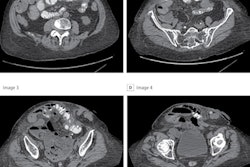

All images were acquired in the supine position on an Ingenuity Elite CT scanner (Philips Healthcare) without contrast. Using coronal CT images obtained from different cross-sections in these patients, the researchers produced a dataset of 1,799 images, which consisted of 790 images for patients with kidney stones and 1,009 of clinically normal subjects. A radiologist and a urologist separately evaluated the images and labeled them as either having kidney stones or no kidney stones.

The authors noted that the algorithm performed well even on small kidney stones. In addition to identifying the presence of kidney stones, the algorithm also successfully marked the areas of interest it used during its decision-making process, according to the researchers.

"Clinically, the regions identified by the model [were] in agreement by our medical experts for most of the images," they wrote. "Hence, our proposed [deep-learning] model is accurate and can assist the radiologists to detect kidney stone cases accurately."